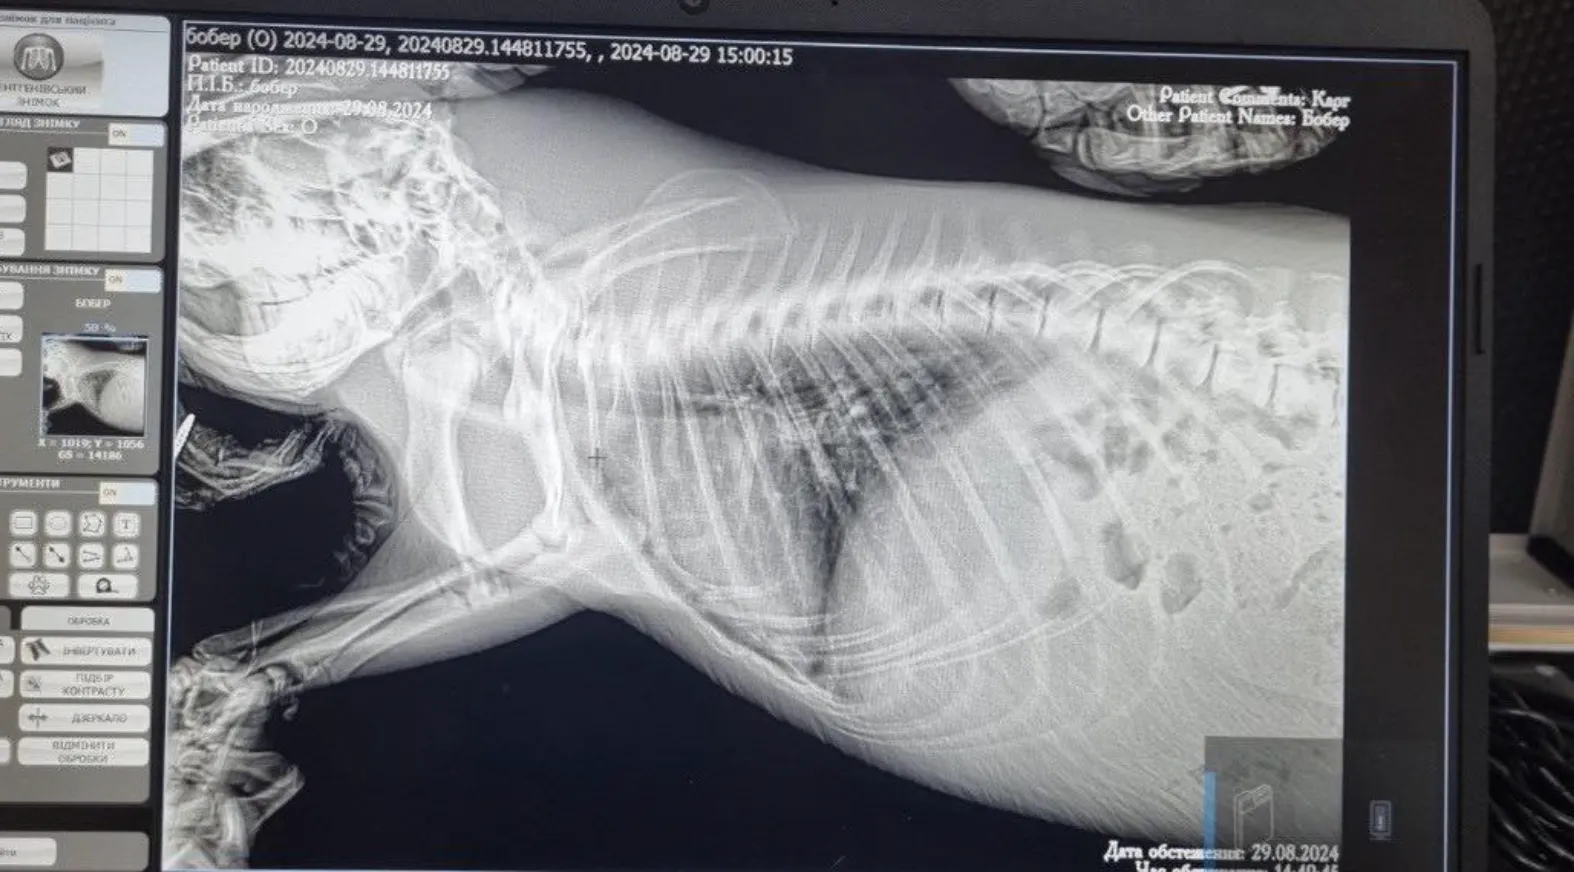

Бобра немедленно повезли в клинику, где диагностировали сильную интоксикацию и отек легких. Врачи оказали помощь, обработали животное и прокапали, после чего он начал двигаться,

Врачи оказали помощь животному и оно начало двигаться / Фото Wild Animals Rescue Center

Состояние бобра тяжелое / Фото Wild Animals Rescue Center